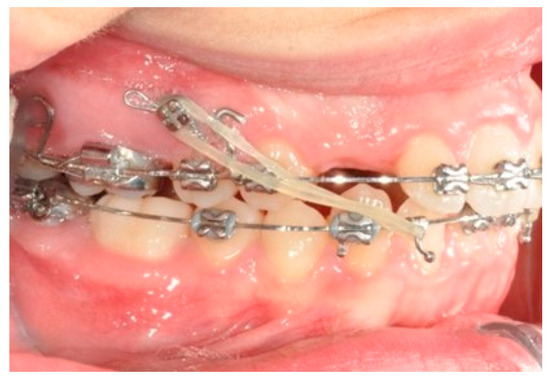

2.3. Canine and Incisor Distalization

In this case, right after the spontaneous eruption, a power chain from the right tad was used to derotate and distalize the right upper canine (Figure 8). On the upper arch, a 0.20 × 0.25 SS wire was prepared with modified “cactus-shaped” closing loops, with the aim to close the space between the canines and the laterals. The cactus loop has a double aim. First of all, it is used as a closing loop; activation is produced by tying the loop through a metallic ligature from the tads. Secondly, it serves as a hook for cantilevers. The cantilevers are made using 0.19 × 0.25 TMA. The retraction of the upper incisors is supported by two cantilevers applied distally on the tads. The cantilevers will support the mechanics in order to produce intrusion of the incisors and torque control during retraction [1] (Figure 9 and Figure 10).

Figure 9. Canine and incisor distalization strategy: The cantilevers produce intrusion of the incisors and torque control during retraction.

Figure 10. Canine and incisor distalization strategy.